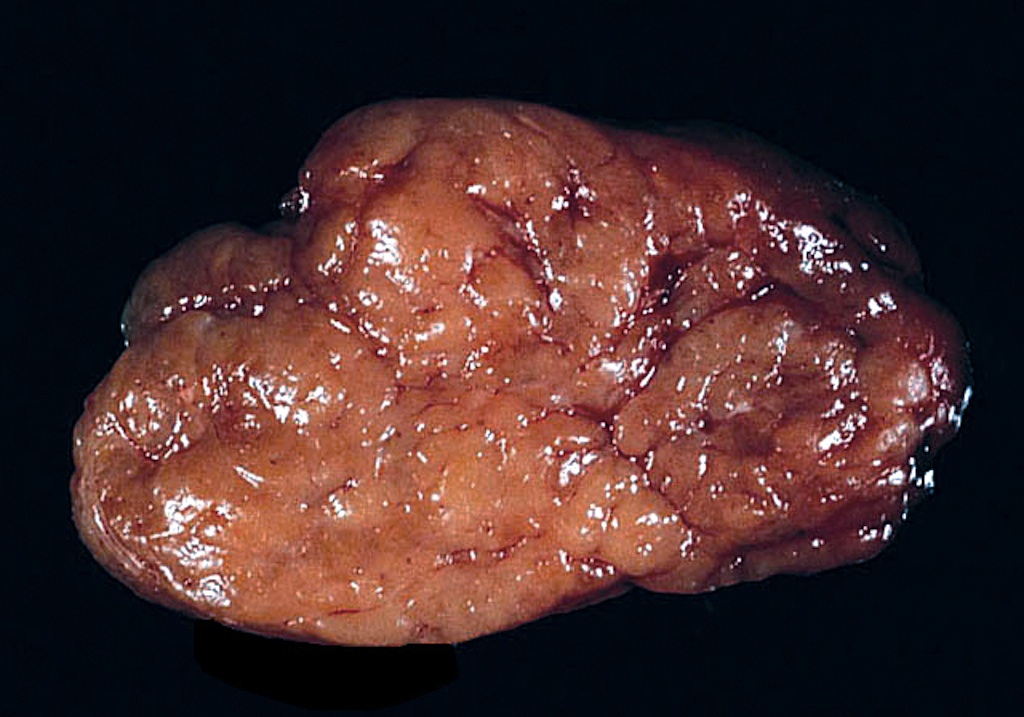

Gross description

- Diffuse symmetric enlargement of thyroid gland; occasionally asymmetric enlargement or nodular

- Cut surface: pale, yellow-tan, firm, nodular; resembles lymph nodes

- May be fibrotic and atrophied

Gross images